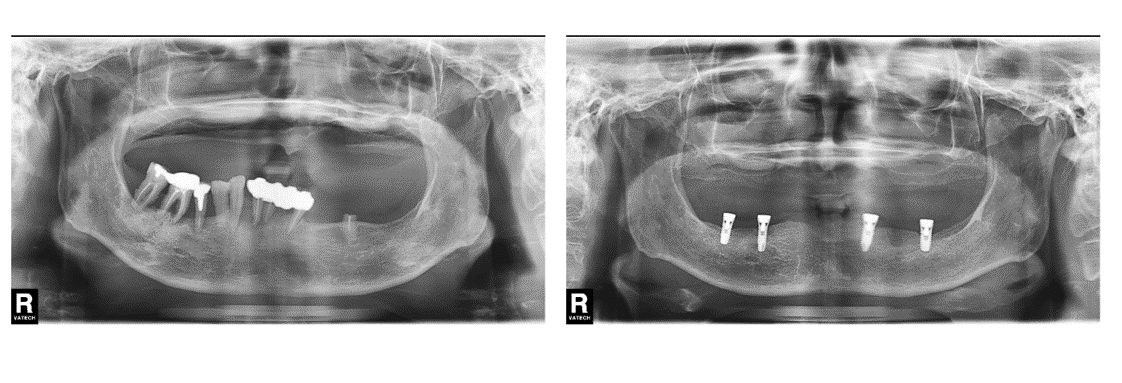

インプラント治療の症例1

(上顎の奥歯と前歯がない)

治療前

治療後

| 診断名・主訴 | ①右上インプラント希望 ②前歯と左上が痛い |

| 年齢 | 45歳 |

| 治療期間 | 2年間 |

| 治療内容 | インプラント治療 |

| 治療に用いた主な材料、設備機器 | 京セラFINESIAインプラント 上部構造:ジルコニアセラミック |

| 抜歯部位 | 左上1・6 |

| 治療費 | 約250万 |

| リスク・副作用 | 術後出血や腫れ |